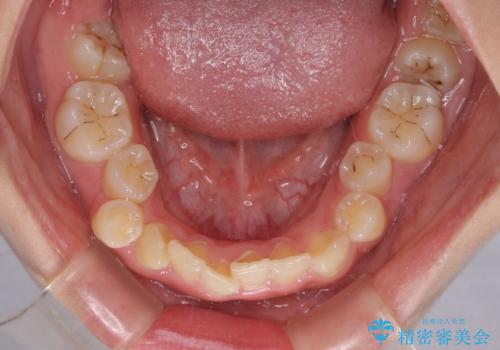

重度叢生と埋もれた奥歯 8本を抜歯したワイヤー矯正

- 内側に生えている歯や埋もれた奥歯を気にして来院された患者様です。

顎の骨が小さいため、歯列が収まりきらずに叢生や未萌出となっている状態でした。

埋もれた奥歯を萌出させ、さらにデコボコを解消するために、上下左右の第1小臼歯4本に加え、親知らず4本も抜歯し、ワイヤー装置にて矯正治療を行うこととしました。